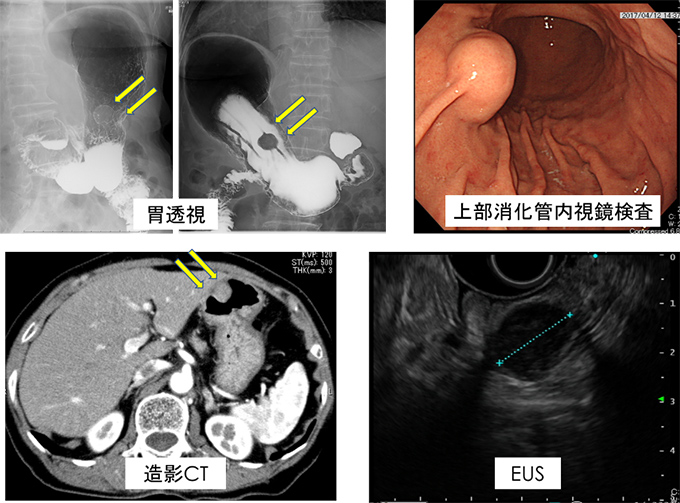

79歳女性。以前より上部消化管内視鏡検査で胃体中部前壁に1cm程度の胃粘膜下腫瘍(SMT)を指摘され経過観察されていました。増大傾向あり(図2)当センター消化器内科に紹介となり、EUS-FNABで消化管間質腫瘍(GIST)の診断となり切除目的に外科紹介となりました。内腔突出型のため(図3)、胃の漿膜面からの腫瘍の正確な位置や大きさ等の確認が困難であり、消化器内視鏡で管腔内からのアプローチも併用する方針となり、LECSを施行しました(図4)。手術時間は3時間20分、出血量は20g、術後2日目より食事開始して術後9日目に退院となりました。

年別上部消化管内視鏡検査の画像:胃体中部前壁のSMTが2010年4月から2013年3月、2016年12月にかけて徐々に増大傾向となっている様子

図2 増大する胃粘膜下腫瘍

胃透視、上部消化管内視鏡検査、造影CT、EUSの画像

図3 術前画像診断